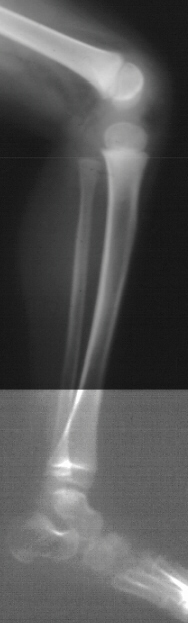

XRAY EVALUATION:

Radiographic examination of the left knee revealed no osseous abnormalities . A fullness of the soft tissues was evident over the fibular head. MRI examination of the left knee displayed a 2 cm. by 0.8 cm. lobulated mass in the region of the common peroneal nerve with no enhancement . On the T-2 weighted sequences there was abnormal increased signal of the tibialis anterior, extensor digitorum longus and peroneus longus muscle bellies suggesting atrophy . EMG/NCS were performed which clearly documented electrodiagnostic evidence of a severe peroneal neuropathy distal to the take-off of the nerve to the short head of the biceps.